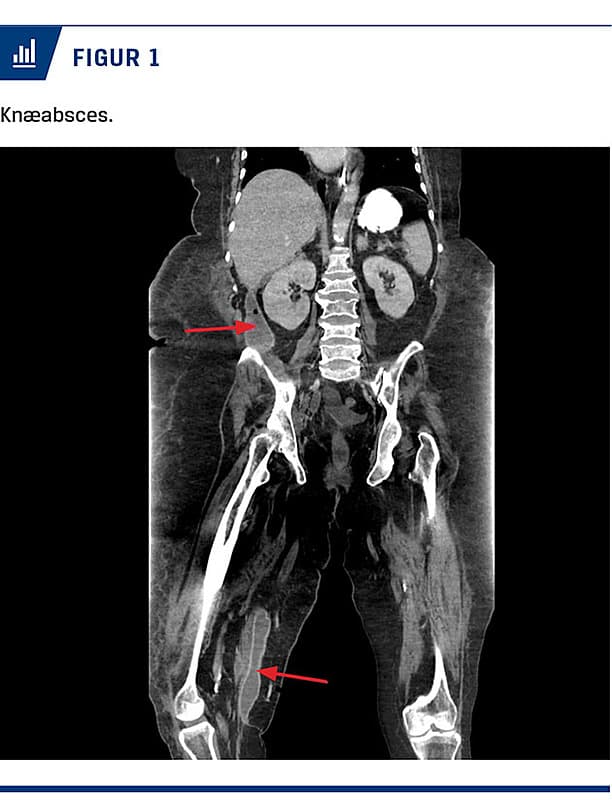

Højre UE hævede yderligere, og 27 dage efter indlæggelse blev der foretaget endnu en CT, som viste tiltagende væskeansamling ved pancreas og i højre fossa, samt multiple abscesser i lårmuskulaturen på højre UE (Figur 1). Ansamlingen i UE blev dræneret lige over knæniveau (Figur 2) med udtømning af 400 ml pus (der indeholdt 34 IE amylase), og ansamlingen i højre fossa blev tømt ultralydvejledt. Begge ansamlinger indeholdt Escherichia coli, hæmolytiske B-streptokokker og Staphylococcus aureus, hvilket medførte et længerevarende behandlingsforløb med firestofsantibiotika. Med tilstedeværelsen af amylase blev abscesserne tolket som sænkningsabscesser gennem retroperitonealrummet ned mod højre UE – altså en ekssudativ pankreatitis.